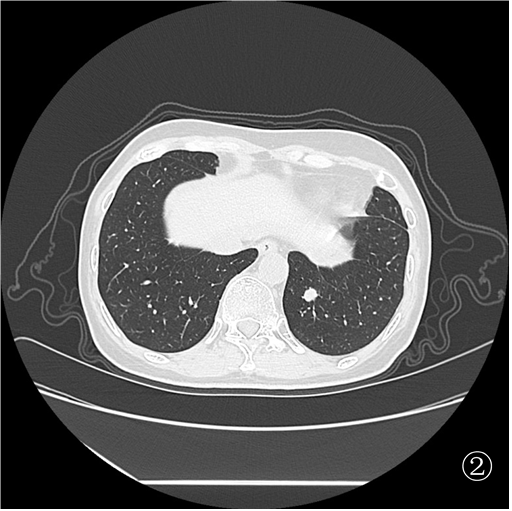

为进一步明确诊断,制定后续治疗方案,杨志祥主任组织讨论后拟行 CT 引导下肺占位穿刺活检,由于右肺占位(图①)毗邻升主动脉及肺动脉,初步拟定行图②左肺占位穿刺活检。

患者俯卧定位扫描(图③):由于胸腔及肺组织受压,左肺占位距离膈肌<1 cm,行穿刺活检必然损伤膈肌,可能造成严重并发症。于是决定经胸前穿刺右肺占位活检(图④),但由于病灶小于 1 cm 且邻近大血管,必须精准制导(图⑤)。穿刺后扫描局部少许出血,未见气胸(⑥)。